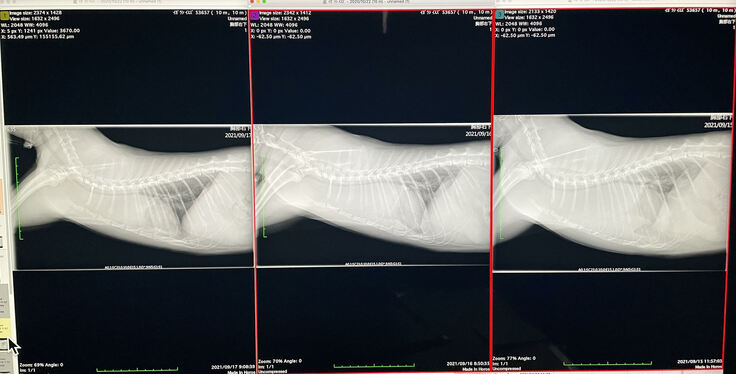

病院でレントゲンを撮ってもらったところ、胸のところに大きな硬い塊があることがわかり、すぐに大きい病院に連れて行くことになりました。

前縦隔リンパ節と腎リンパ節に大きな腫瘍がありました。

※右から入院直後、抗がん剤1回目、2回目